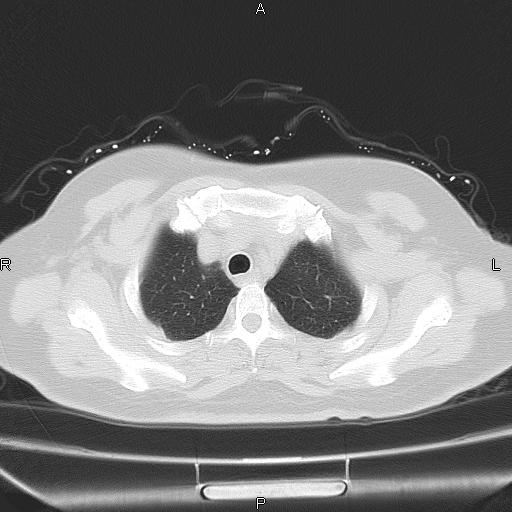

胸腺瘤

女、63Y 双眼睑下垂,早轻晚重。 胸腺瘤???

结果胸腺瘤